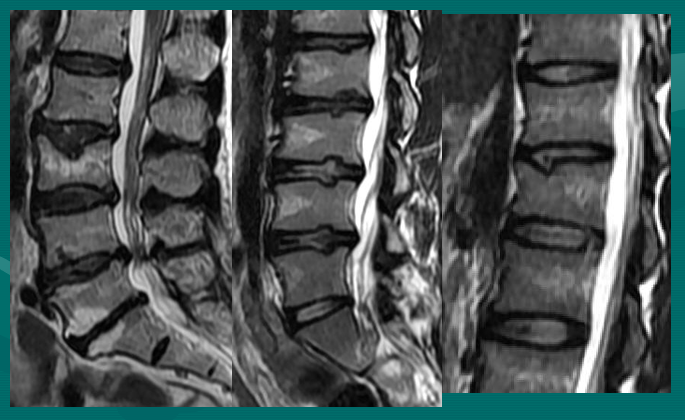

正常腰椎间盘表现

正常腰椎间盘后缘不超过椎体骨性终板的后缘,且中部略有凹陷呈肾形。